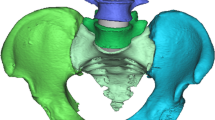

The finite element model used in this study was adapted from the Spine Model for Safety and Surgery (SM2S), which was previously used in trauma and medical device biomechanical studies similar to the present context of use and validated through comparison with published experimental data [11, 12]. The pelvis was reconstructed in 3D using a series of cross-section images of the pelvis of a 50th percentile human volunteer (32-year-old Caucasian male, 75 kg, 1.75 m, with no known spinopelvic pathology) [13]. The pelvic bony structures were modeled as trabecular cores enveloped by the cortical external layer with region-specific thickness taken and adapted from the literature [13, 14]. The cortical layer of the iliac bones had regional thicknesses ranging from 0.3 to 5 mm and the sacral cortex was 1 mm thick (Fig. 1). Trabecular and cortical bones were meshed using four node tetrahedral elements of 0.4 mm characteristic length near the contact zone with the screw shaft and where there were significant topologic and geometric changes (sharp change of local surface orientation, small radius of curvature, etc.). Greater characteristic lengths (around 1 mm) were used elsewhere to reduce the computational load. The screw external surface was modeled as a two-dimensional (2D) shell meshed with characteristic triangular elements of 0.4 mm. The triangle-based elements were chosen for their ability to comply with complex geometry and their non-warpage properties. The final mesh density and distribution was confirmed by a convergence study. The trabecular core and the cortical external layer were bonded through sharing common nodes along their contact surface. The screw was considered as rigid body, as its Young’s modulus is far higher than those of the cortical and cancellous bones. The sacroiliac junction was modeled as a bicondylar joint in close-packed position with realistic physiologic motion [15, 16]. The pubic symphysis was represented as a single cartilaginous solid. The major pelvic ligaments (interosseous, sacroiliac anterior, sacroiliac posterior, sacrotuberous and sacrospinous) and pubic symphysis geometries were directly implemented from anatomic descriptions [17, 18]. The same method was used to create a control model of the L5 vertebra.

Posterior (a) and anterior (b) view of the ilia with areas of different cortical thicknesses and posterior (c) and left (d) view of the instrumented sacroiliac joint including the interosseous ligament (1), anterior sacroiliac ligament (2), cartilage (3), sacrospinous ligament (4), sacrotuberous ligament (5) and pubic symphysis (6)